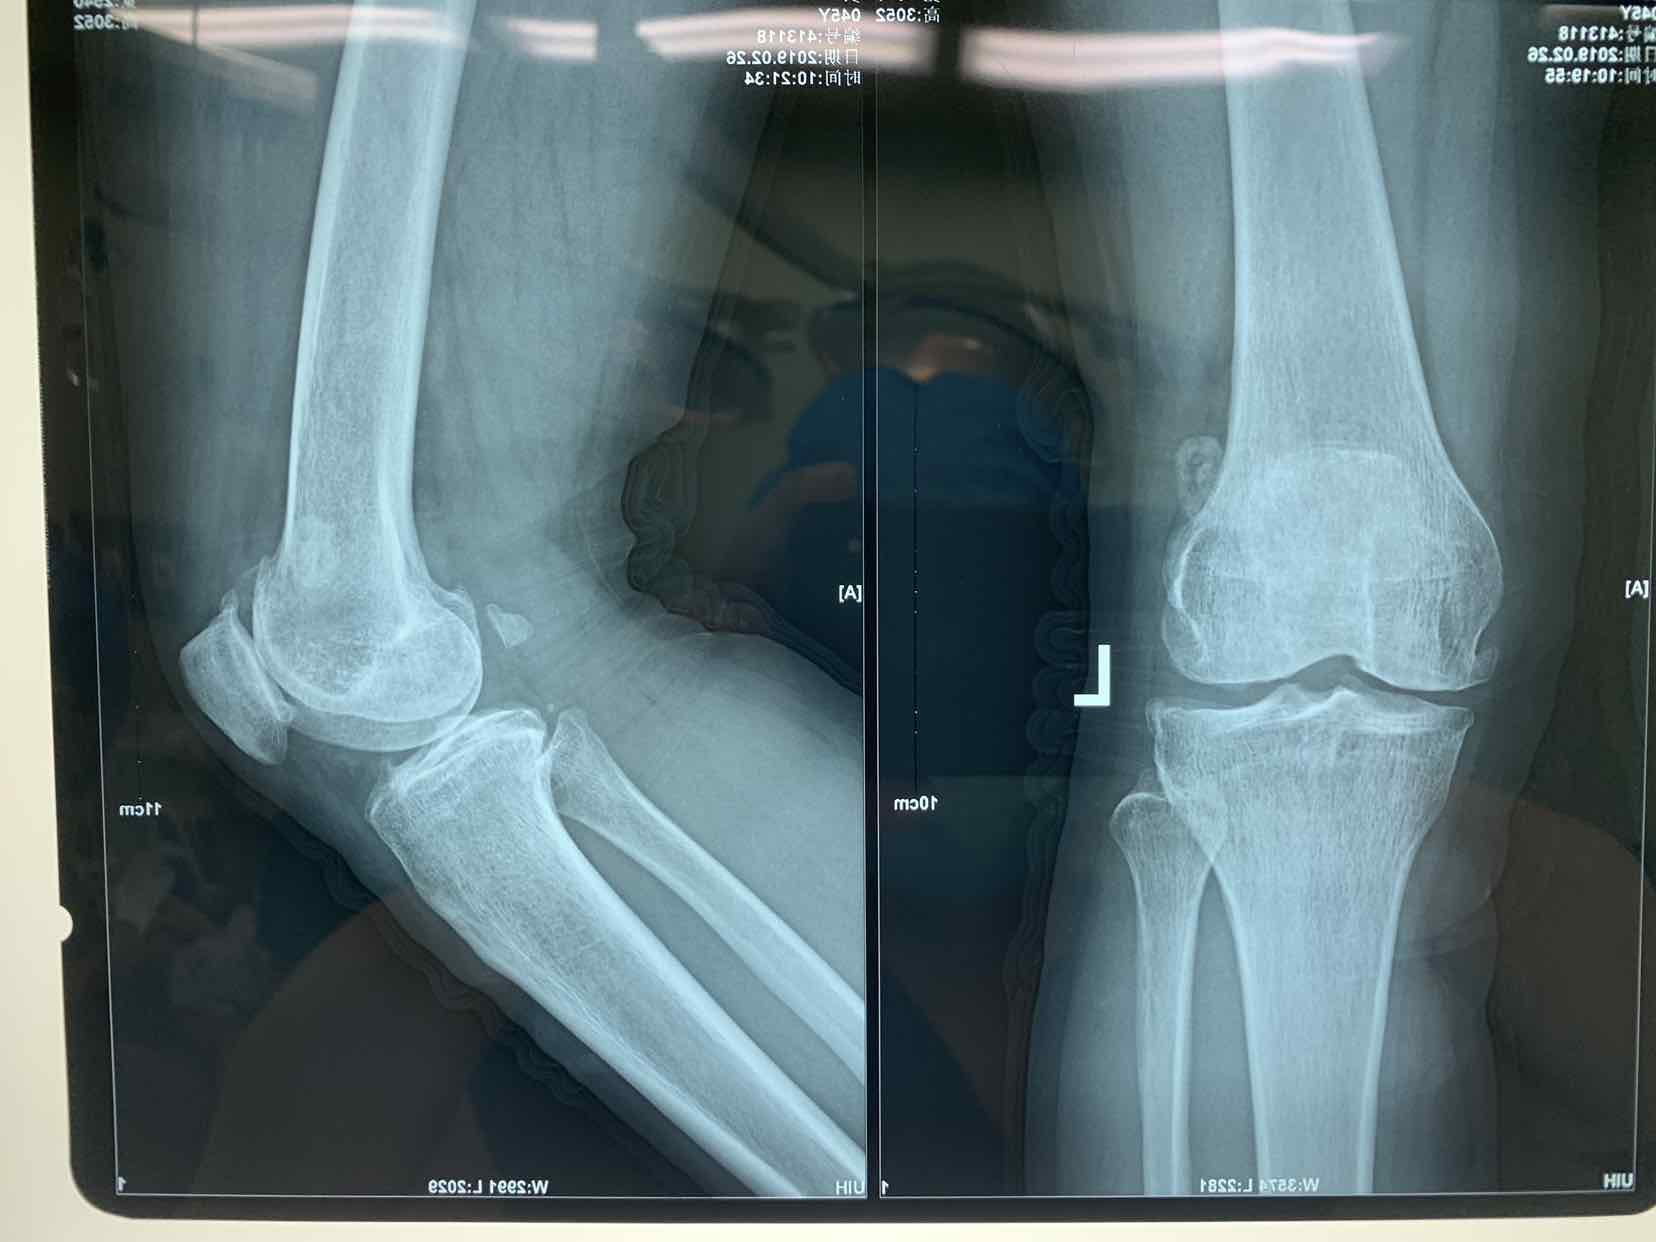

患者因双侧膝关节骨性肿物发现二十余年。收入院。患者无二十余年前无明显诱因发现双侧膝关节内有骨性肿物。异常活动。偶尔在屈曲活动时出现局部嵌夹于关节内。疼痛。不能活动。并弹响。近半年内肿物增大。疼痛发作频繁。遂来诊。门诊拍片提示见双侧膝关节内骨性游离体,位于关节内。门诊以双侧膝关节游离体收入院。

查体见患者双侧膝关节局部肿胀。压痛。可于局部触及骨性肿物在关节内游走。屈伸活动时偶有嵌顿。行走活动受限。拍片提示双侧膝关节骨性游离体。

诊断为双侧膝关节游离体。再局麻下银行膝部游离体取出术。术后患者恢复良好。

膝关节游离体是临床常见疾病。可以通过关节镜探查发作。拍片或者核磁共振检查也可获得可靠诊断。处理非常简单。发现肿物挤压至一侧。切口就可以取出。